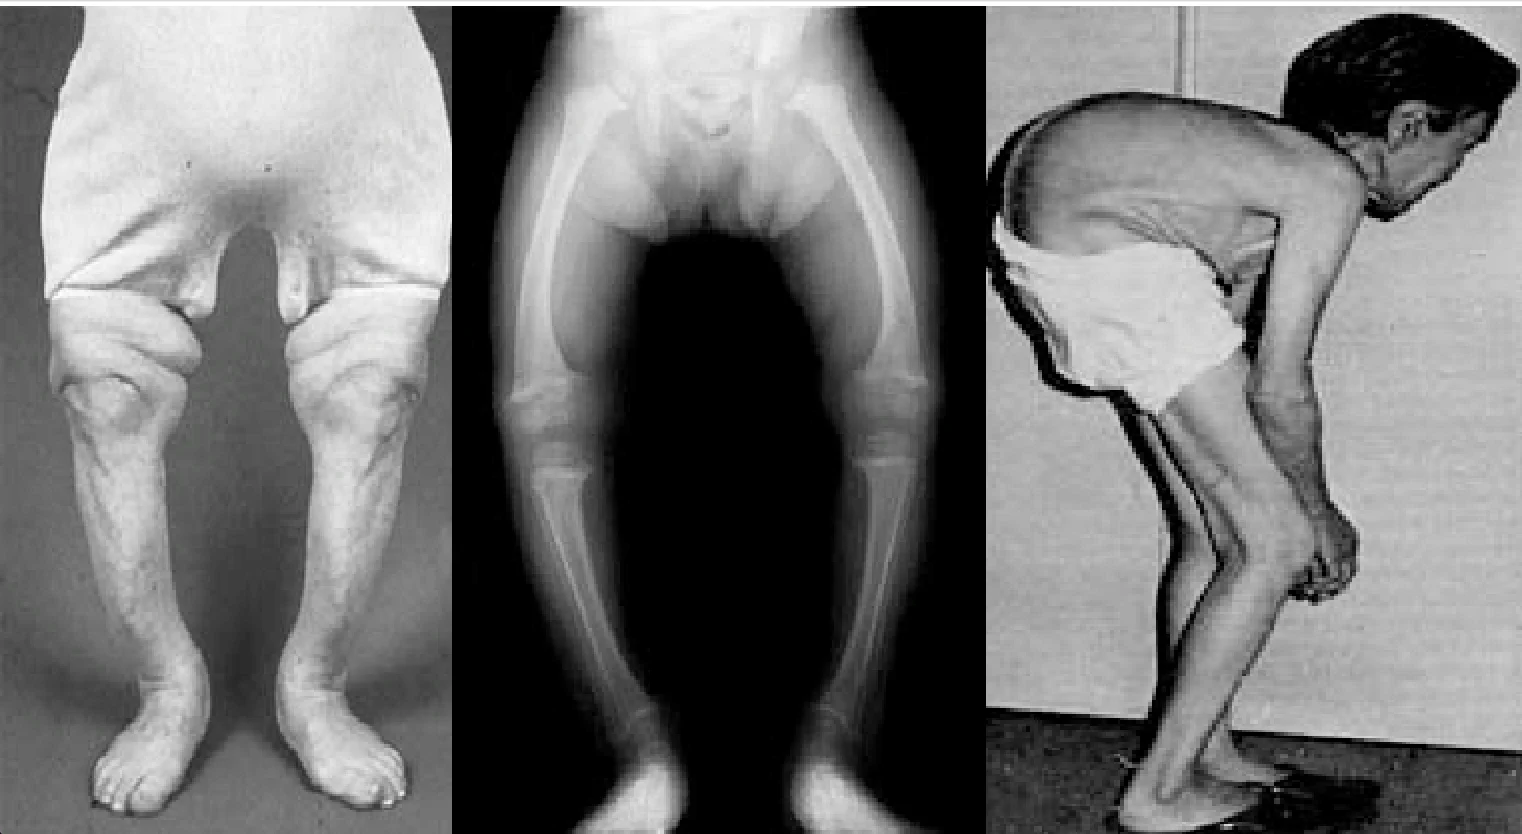

ซึ่งไม่ใช่แค่ไตล้มเหลวเท่านั้น แต่โรคนี้ยังทำให้เกิดภาวะอื่น อย่าง กระดูกอ่อน ผุ เปราะง่าย คล้ายกับโรคกระดูกนิ่ม หรือที่ภาษาทางการแพทย์เรียกว่า osteomalacia ซึ่งเป็นภาวะสืบเนื่องกับการทำงานผิดปกติของไต

และอาการเจ็บปวดจากข้างในที่ว่ากันว่า เจ็บเหมือนการถูกยิง แต่สิ่งที่แย่กว่านั้นคือ หากถูกระบุว่าเป็นโรคอิไต-อิไต ตามการบันทึกระบุว่า อัตราการรอดชีวิตของผู้ป่วยโรคนี้อยู่ในระดับที่ต่ำ และส่วนใหญ่คนที่เป็นโรคมักพบในผู้หญิงที่มีอายุมากกว่า 50 ปี เช่นเดียวกันกับผู้หญิงตั้งครรภ์ที่อาศัยอยู่ในพื้นที่นานกว่า 30 ปี